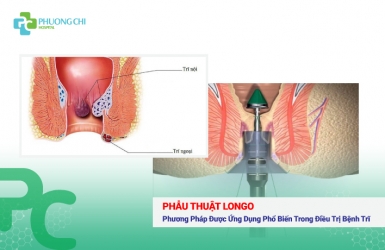

Phẫu Thuật Longo: Phương Pháp Được Ứng Dụng Phổ Biến Trong Điều Trị Bệnh Trĩ

Trĩ là một bệnh rất phổ biến hay gặp ở người lớn, hiếm gặp ở trẻ em. Tuy bệnh ít nguy hiểm nhưng gây nhiều trở ngại, phiền phức trong sinh hoạt, từ đó ảnh hưởng đến năng suất lao động, chất lượng công tác và tâm sinh lý của người bệnh.